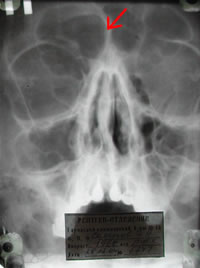

Как выглядит фронтит на снимке?

Воспаленная лобная пазуха выглядит на рентгенограммах следующим образом: